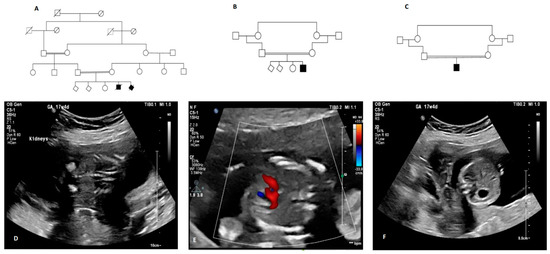

| Family 1 | Yes | 2 | Antenatal presentation (17 weeks gestation) Bilateral echogenic kidneys Congenital heart defects Situs inversus of the heart and the intestines | Termination of pregnancy at 17 weeks | chr9:g.98782527T>G | ANKS6: c.1159A>C | p.Thr387Pro | Homozygous | Possibly Damaging (0.917) | Damaging (0.011) | 23.1 | VUS (PM1, PM2) |

| Family 2 | Yes | 2 | Neonatal presentation Bilateral enlarged cystic kidneys Congenital hepatic fibrosis Ascites, Cholestasis Systemic hypertension Portal hypertension | Infant death at 7 months of age | chr9:g.98782527T>G | ANKS6: c.1159A>C | p.Thr387Pro | Homozygous | Possibly Damaging (0.917) | Damaging (0.011) | 23.1 | VUS (PM1, PM2) |

| Family 3 | Unknown | None | Antenatal presentation (21 weeks gestation) Bilateral enlarged cystic kidneys Multiple congenital anomalies Distended abdomen Bilateral talipes equinovarus deformity | Neonatal death (1 day) | chr9:g.98784830A>T | ANKS6: c.907+2T>A | p.? | Homozygous | N/A | N/A | 32 | Pathogenic (PVS1, PM2, PP3, PP5) |